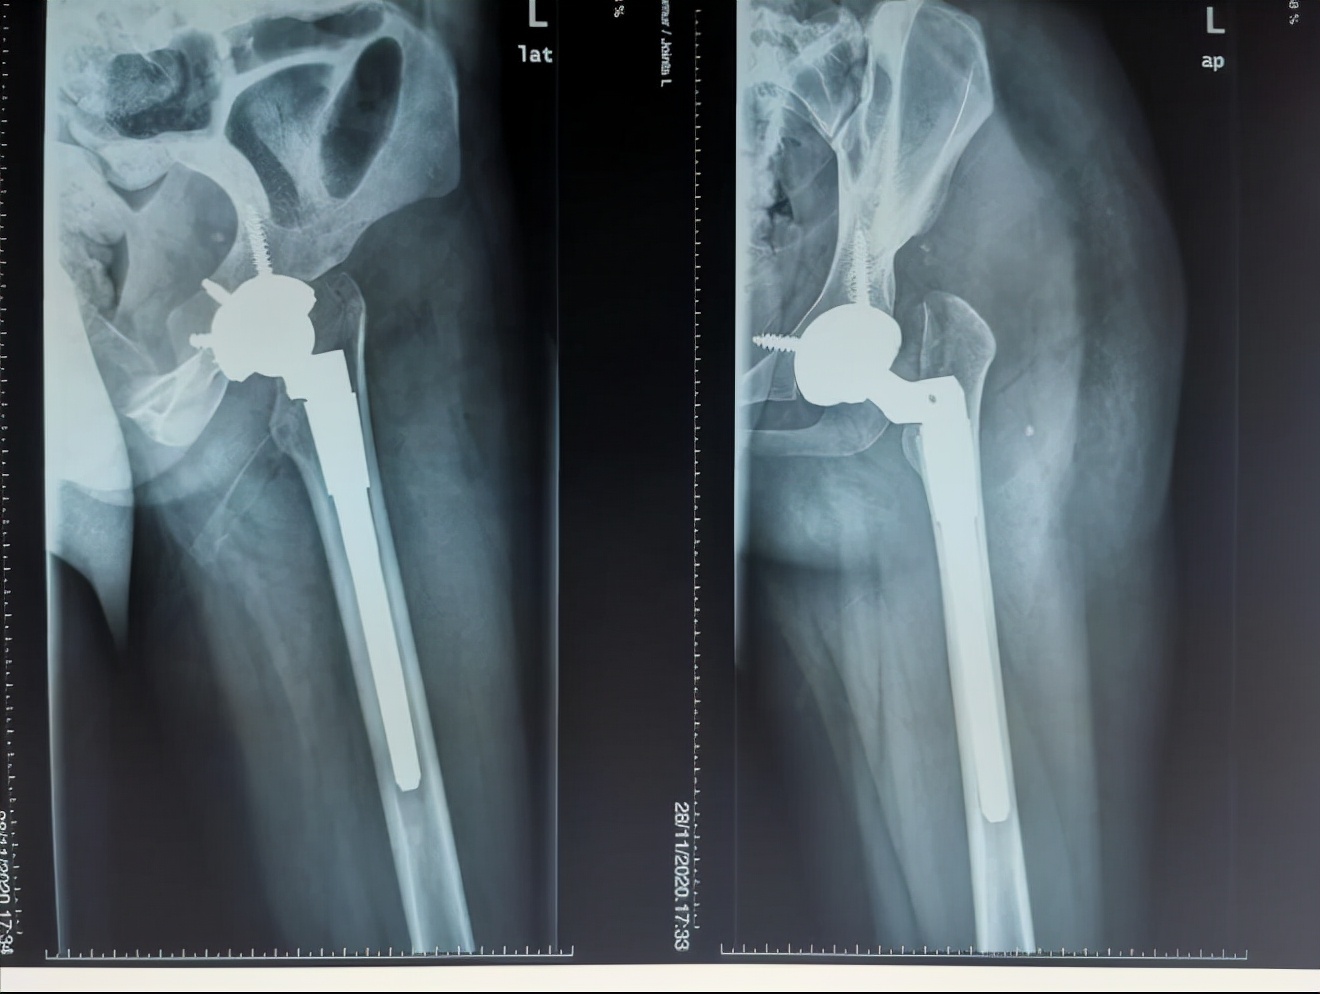

通过术前充分的准备,小张的手术也如约而至。当天在术中,毕教授和耿教授发现小张的患侧股骨头和髋臼都存在发育异常,没有软骨而且形状较不规则,难以契合,保髋方案不可取,于是只能采取方案二:全髋关节置换术。因为术前提前进行了规划,相应型号的假体也已经提前准备,髋臼假体及股骨假体安装得较为顺利。然而和预料的一样,在髋关节假体尝试复位时软组织张力较大,很难进行复位。因为在术前患侧股骨通过极限力量牵引验证了不截骨复位的可能性是存在的,为了能够让患者一期恢复腿长,避免二次手术,毕郑刚教授和耿硕副教授决定通过进行软组织的松解来复位,选择了不进行股骨截骨,但是考验手术技术。经过对髋关节周围软组织的松解后,最终假体复位成功,随后通过比对双下肢长度,提示等长,关节活动度良好,宣告着手术一期顺利完成。术后小张返回病房后,因为未进行截骨仍有软组织张力大致神经血管等损伤的风险,术后嘱其行患肢适度屈髋屈膝位来减缓软组织张力,2~3周内逐渐伸直。术后通过查体,小张并未出现神经的损伤症状,手术圆满成功。

(术后X线)